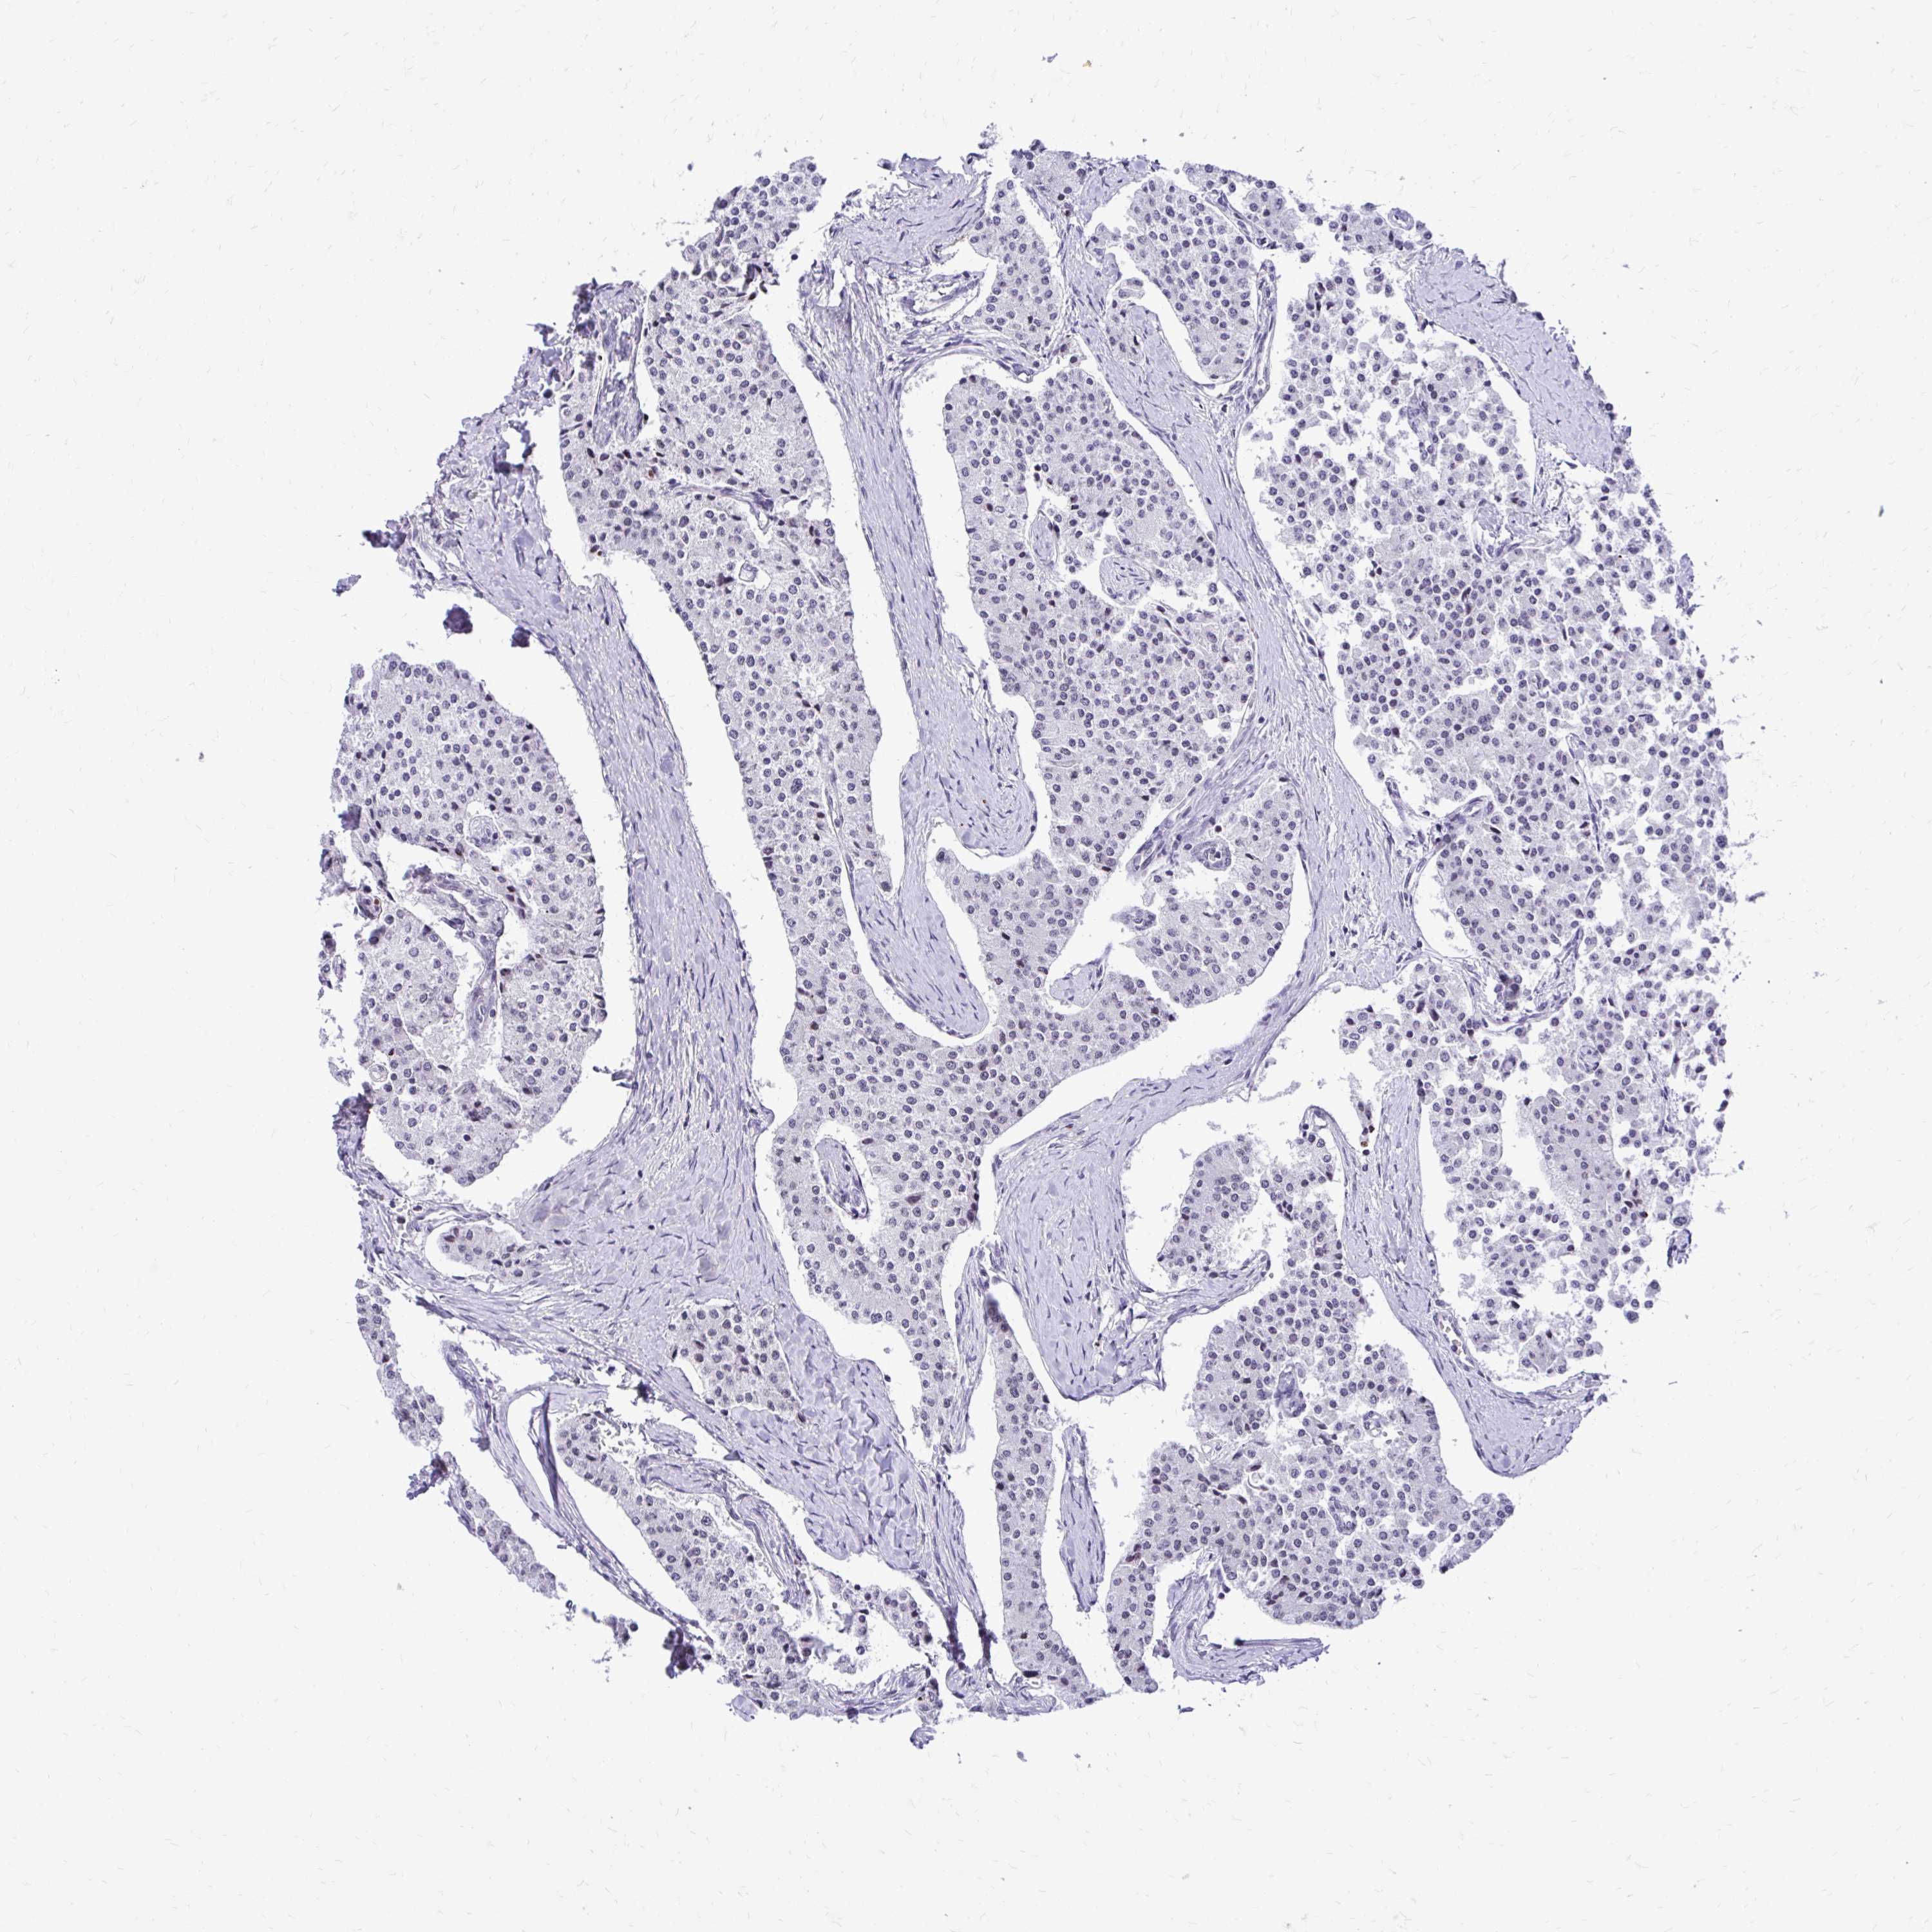

CARCINOID - Protein expressioni

A mouse-over function shows sample information and annotation data. Click on an image to view it in a full screen mode. Samples can be filtered based on level of antibody staining by selecting one or several of the following categories: high, medium, low and not detected. The assay and annotation is described here.

Antibody stainingi

Antibody staining in the annotated cell types in the current human tissue is reported as not detected, low, medium, or high, based on conventional immunohistochemistry profiling in selected tissues. This score is based on the combination of the staining intensity and fraction of stained cells.

Each image is clickable and will lead to virtual microscopy that enables deeper exploration of all samples and also displays staining intensity scores, fraction scores and subcellular localization as well as patient and tissue information for each sample.

Antibody CAB032896

Staining

High

Intensity

Strong

Quantity

>75%

Location

Nuclear

Carcinoid, malignant, NOS